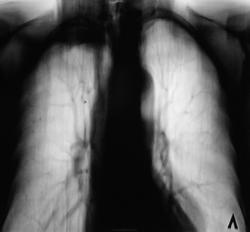

Пол пациента: Мужской пол Тип патологии: Другое Область исследования: Грудная клетка и верхние дыхательные пути Методы исследования: Rg Контроль после флюорографии. Верхушка вызвала недоверие https://radiomed.ru/sites/default/files/styles/case_slider_image/public/user/12/6.dscn0396.jpg?itok=dcnuKHCZ https://radiomed.ru/sites/default/files/styles/case_slider_image/public/user/12/7.dscn0396a.jpg?itok=wfK2iVjR ID:23836 Sun, 21/10/2012 - 12:17 #1 maker4ik Offline Last seen: 8 years 9 months ago Joined: 19.10.2011 - 17:49 Posts: 2682 Панкост? Sun, 21/10/2012 - 19:46 #2 И.Бондаренко Offline Last seen: 14 hours 57 min ago Joined: 13.09.2011 - 22:55 Posts: 9208 Возраст пациента? Sun, 21/10/2012 - 22:23 #3 Катенёв Валенти... Offline Last seen: 7 years 3 months ago Joined: 22.03.2008 - 22:15 Posts: 54876 В районе 50 лет. Mon, 22/10/2012 - 09:13 #4 Андрей Багаев Offline Last seen: 11 years 4 months ago Joined: 28.01.2011 - 19:14 Posts: 57 а 1 ребро целое? Mon, 22/10/2012 - 22:48 #5 И.Бондаренко Offline Last seen: 14 hours 57 min ago Joined: 13.09.2011 - 22:55 Posts: 9208 За периферический Tue, 23/10/2012 - 00:50 #6 Петрович Offline Last seen: 7 years 5 months ago Joined: 22.03.2009 - 01:13 Posts: 3908 Скорее воспалительная инфильтрация с мощной плевральной реакцией. Архив есть? Неоднозначно всё

Панкост?

а 1 ребро целое?

За периферический

Скорее воспалительная инфильтрация с мощной плевральной реакцией.